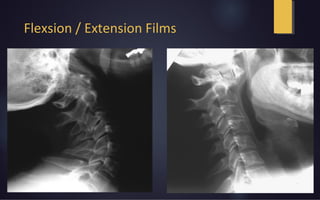

Flexsion / Extension Films

Rotation on CT scan



Able to visualizing rotation and associated fractures

Dynamic CT scans are not advocated

- Risk of inducing neurological injury secondary to instability

Standard measurement technique for rotational angle